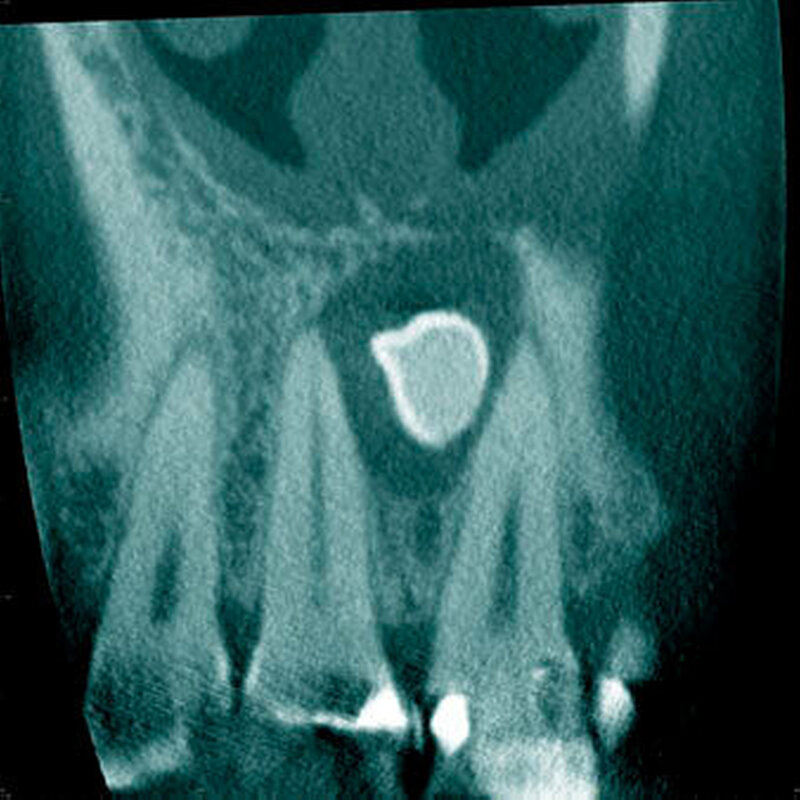

In einer aktuellen Arbeit berichteten Mossaz und Mitarbeiter (2014) über eine relativ hohe Prävalenz (22,8 Prozent) der Wurzel- resorptionen an benachbarten Zähnen, wobei besonders häufig überzählige Prämolaren zu Resorptionen führen (Abbildung 18). Für die Beurteilung der Wurzelresorptionen wurden digitale Volumentomografie (DVT) der Patienten herangezogen. In einer Studie aus China, welche ebenfalls DVT-Bilder beurteilte, wurde über eine deutlich geringere Häufigkeit von Wurzelresorptionen (1,6 Prozent) berichtet [Liu et al., 2007]. Im Gegensatz zu den Daten aus der Schweiz war Diagnose und Bewertung von Wurzelresorptionen kein primäres Ziel dieser Studie und es wurde auch keine Information über das Ausmaß der Resorptionen gegeben.

Daher könnte diese Studie leichte oder mäßige Wurzelresorptionen nicht eingeschlossen haben, was zumindest einen Teil des doch deutlichen Unterschieds in den Prozentsätzen erklären würde. Studien, welche Panoramaschichtaufnahmen zur Diagnose von Wurzelresorptionen heranziehen, berichten über Resorptionsraten zwischen 4,7 Prozent [Gündüz et al., 2008] und 7,6 Prozent [Hyun et al., 2009]. Tyrologou und Mitarbeiter (2005) berichteten sogar, dass keine Resorption im untersuchten Patientengut vorhanden waren. Allerdings wurden in dieser Studien nur Mesiodentes beurteilt, wo Wurzelresorption benachbarter Zähne eher selten vorkommen [Mossaz et al., 2014]. Generell lässt sich festhalten, dass zweidimensionale Röntgenaufnahmen für die Diagnose von Wurzelresorptionen eher ungenau sind und diese so in bis zu 50 Prozent der Fälle übersehen werden [Ericson Kurol, 1987, Heimisdottir et al., 2005; Botticelli et al., 2011; Alqerban et al., 2011a].